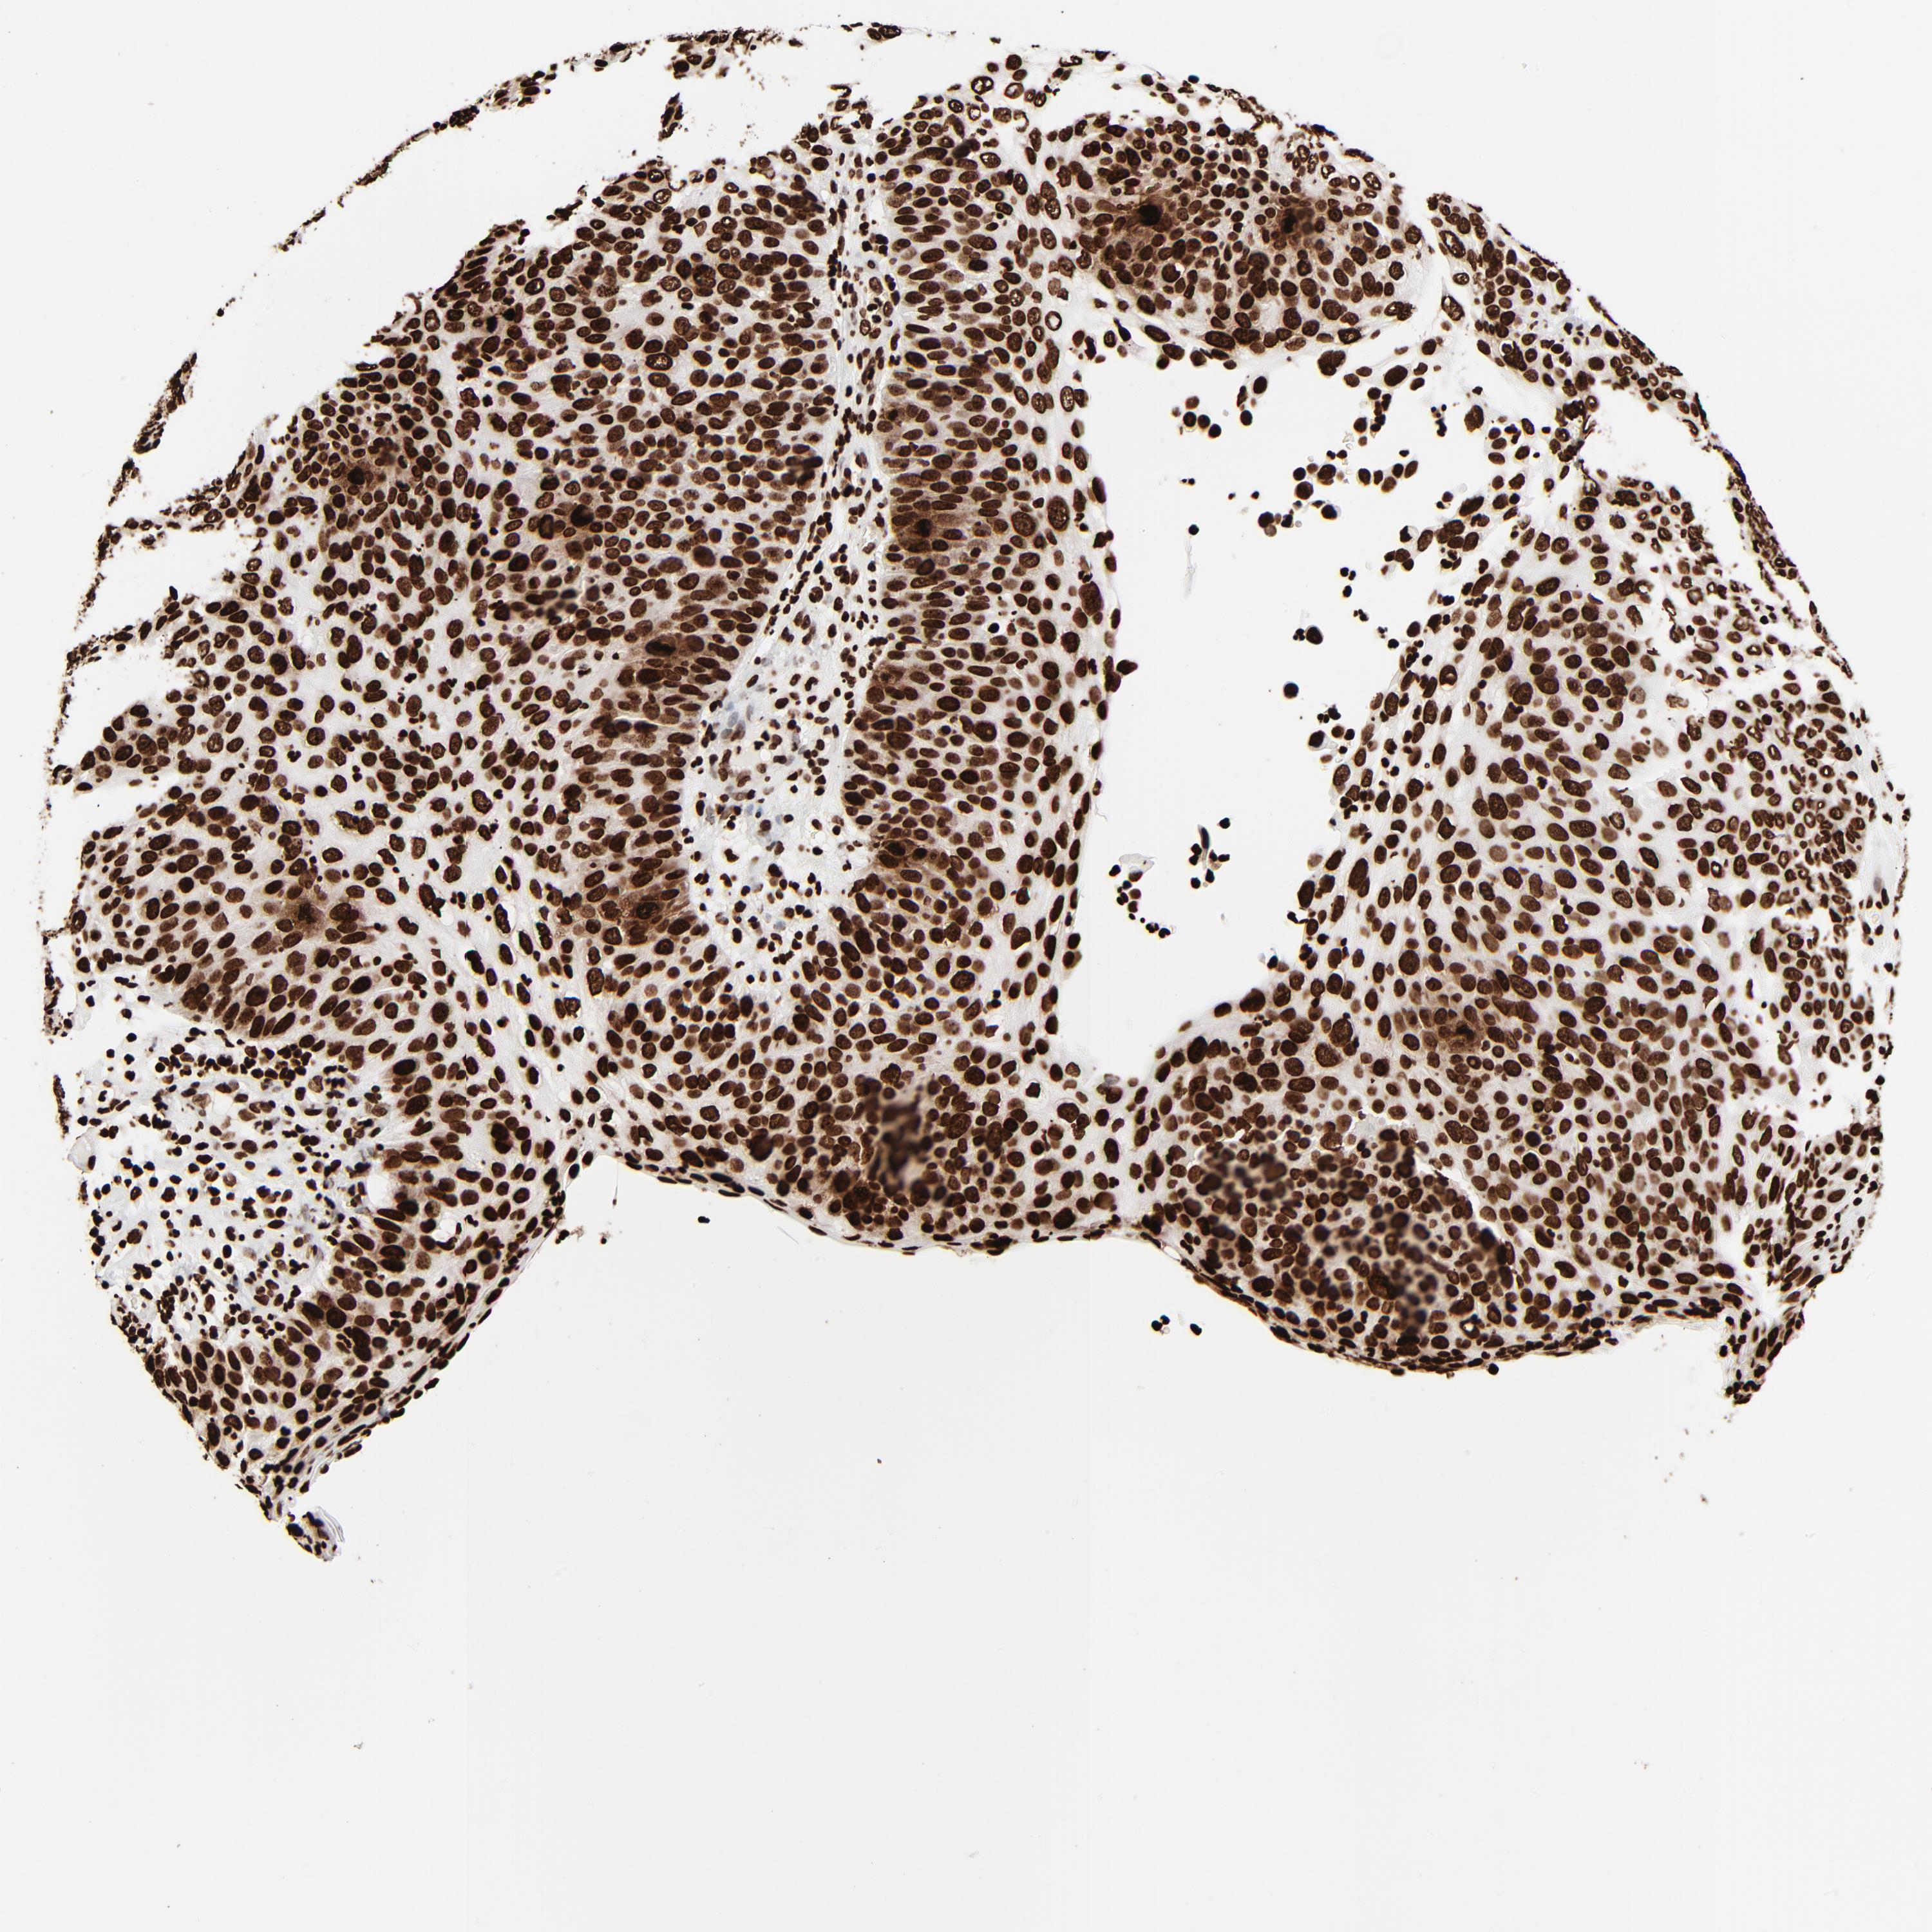

SKIN CANCER - Protein expressioni

A mouse-over function shows sample information and annotation data. Click on an image to view it in a full screen mode. Samples can be filtered based on level of antibody staining by selecting one or several of the following categories: high, medium, low and not detected. The assay and annotation is described here.

Each image is clickable and will lead to virtual microscopy that enables deeper exploration of all samples and also displays staining intensity scores, fraction scores and subcellular localization as well as patient and tissue information for each sample.

Antibody CAB001386

Squamous cell carcinoma, NOS